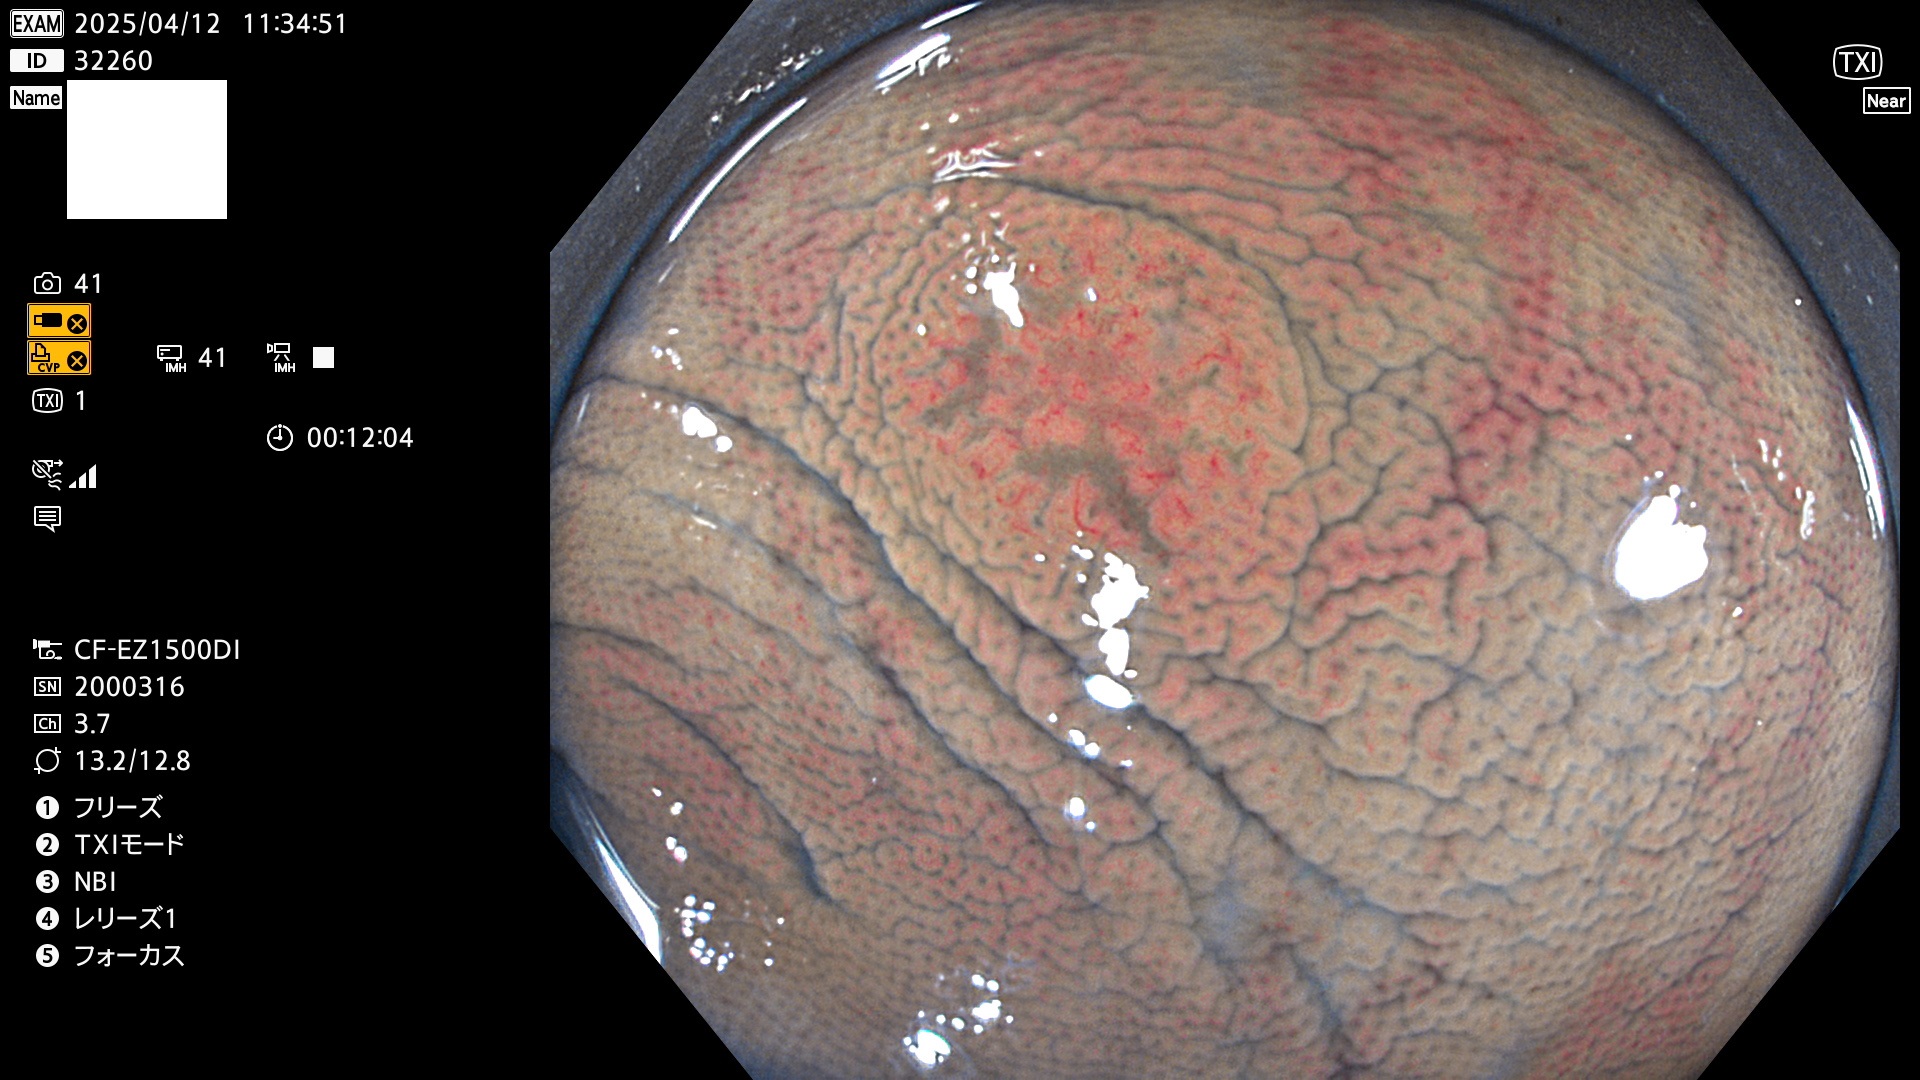

抽出の対象期間 2025年4月10日〜4月13日の4日間(48件の検査)11個 (4/48=23%)

びらんと鑑別の困難なUc型腺腫